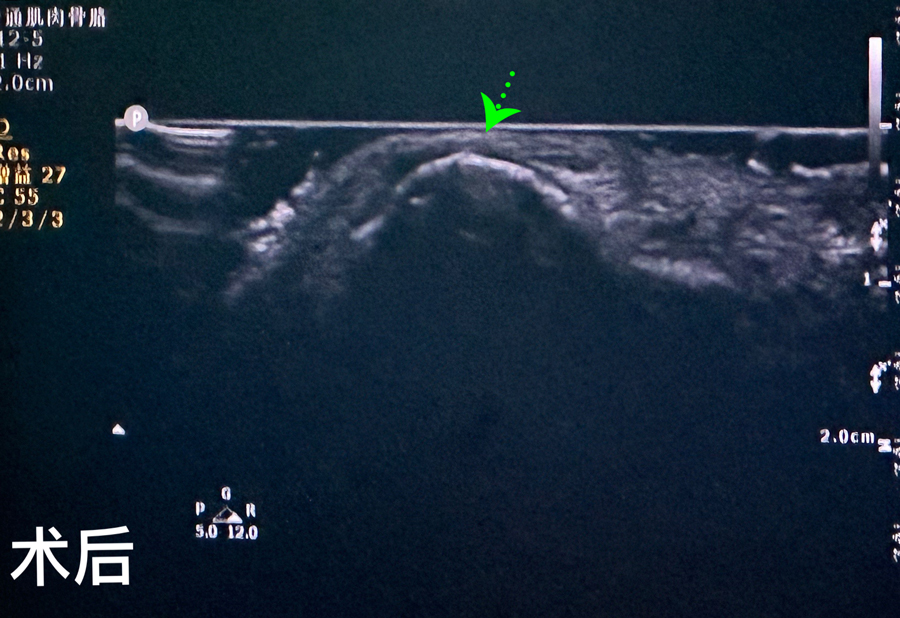

8月15日,彬彬家长在辗转多家医院后,听说德州扑克游戏网 有鼻骨骨折复位新技术,立即带彬彬赶到医院。此时,距离彬彬鼻骨骨折已经过去一周了。就诊时,彬彬鼻部肿胀已经消退了,能看到他的鼻梁是向左侧偏曲的,妈妈特别希望孩子的鼻梁能恢复到从前高挺、居中的状态。国家儿童医学中心、北京儿童医院耳鼻喉头颈外科常驻专家、德州扑克游戏网 副院长张薇,德州扑克游戏网 耳鼻喉科主任李莉萍为其进行鼻部检查,并结合鼻骨CT全面评估后,决定采用超声引导下鼻骨骨折复位术,以实现精准复位,使彬彬的面容不受影响。8月16日,张薇副院长、李莉萍主任及手术室、麻醉科医护人员组成手术团队,为彬彬进行手术。术中,医生在超声引导下应用复位器对游离骨片进行复位调节,使错位的鼻骨重新连续。10分钟后,手术顺利完成,复位后的鼻子外观无畸形。术后,彬彬接受抗感染治疗48小时,情况稳定,顺利出院。

相比较传统凭经验及手感的鼻骨复位术,超声引导下的手术复位能更精准定位到损伤部位,如医生的“透视眼”,实现手术可视化,使医生在术中可准确看到鼻骨断端的对合情况,在“精准、微创、美观”上得到极大优化和提升。患儿无伤口、恢复快。术前和术后鼻骨错位及对合情况B超均有图片准确显示,让家长也能看明白,患儿和家长的心理负担明显减轻不少,改善了就医体验。